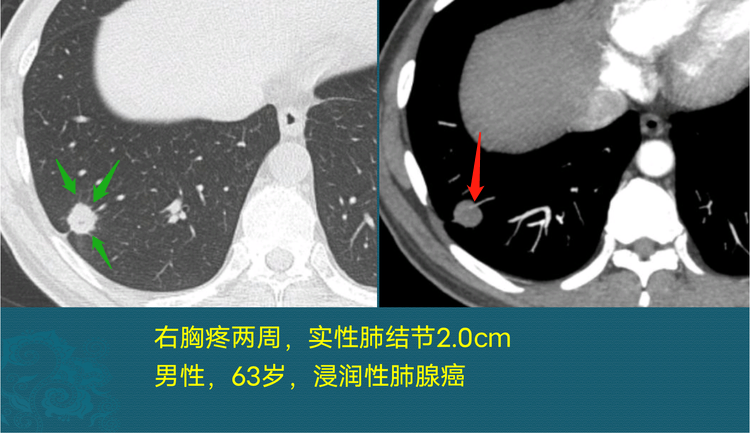

恶性肺结节图片,实性结节

实性结节

恶性肺结节ct图片

恶性肺结节